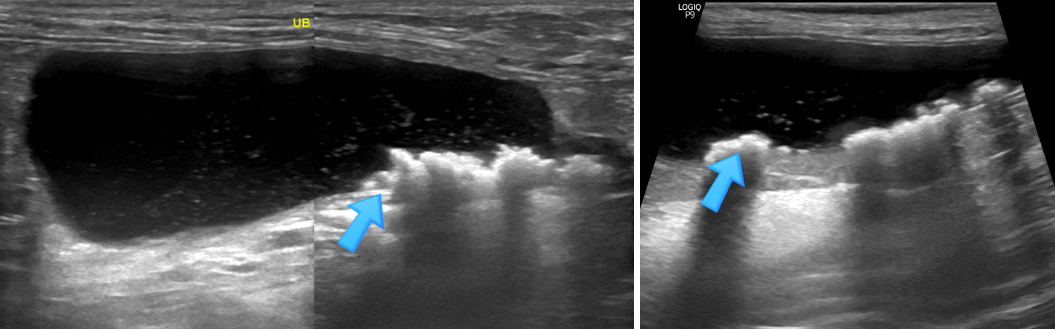

말티즈 친구의 복부초음파 사진입니다.

방광에 슬러지와 함께

다량의 결석이 확인이 되었습니다.

"수컷강아지는

결석이 요도를 막게될 경우

위험할 수 있습니다"

수컷 강아지는

방광에서 결석이 내려와

요도를 막을 경우

통증으로 인해 기절, 경련 등의 증상을 보일 수 있고

심할 경우 위험한 상황이 올 수 있기때문에